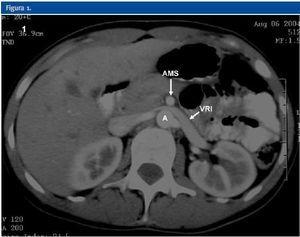

La ecografía Doppler, al igual que la TC realizada, demostró la compresión de la vena renal izquierda entre la arteria mesentérica superior (AMS) y la aorta abdominal (A). En la ecografía Doppler se demostraba un efecto de pinza sobre la vena renal principal izquierda (VRI) que se traducía en una asimetría de flujo venoso entre ambos riñones, siendo de amplitud y pulsatibilidad disminuída en el lado izquierdo. Se observaba también circulación colateral retroaórtica (CCR) con inversión de flujo en la vena ovárica izquierda. En la TC se evidenciaba circulación colateral retroaórtica (vena renal retroaórtica accesoria).

Figura 3.